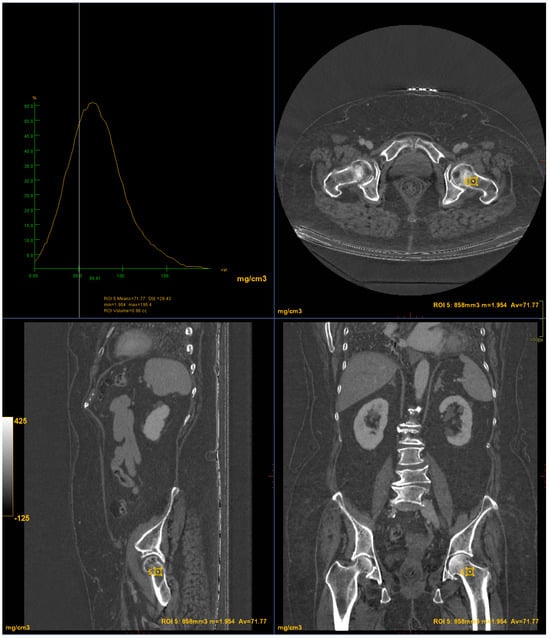

DXA scans were performed using a bone densitometer (Discovery A, HOLOGIC, Marlboroug, MA, USA) for the lumbar vertebrae (L1 to L4) and femoral neck (Figure 1 and Figure 2).

Figure 1. DXA measurements on the lumbar vertebrae (Regione: measurement region; Area: measurement area; BMC: Bone Mineral Content; BMD: Bone Mineral Density; PR: Reference peak; AM: Age Matched).

CT images were processed using AW3.2 software (GE Healthcare, Chicago, IL, USA) with a bone window and HAP–fat base material pairing, which highlights structures containing hydroxyapatite. Three-dimensional volume of interest (VOI) measurements were obtained at the lumbar vertebrae (Figure 3) and femoral neck (Figure 4), sampling the trabecular bone while excluding cortical bone regions.

Figure 3. DECT measurements on the lumbar vertebrae (ROI1: L4 measurement; ROI2: L3 measurement; ROI3: L2 measurement; ROI4: L1 measurement). The ROI volume was 858 mm3.

Figure 4. DECT measurements on the femoral neck (ROI5: femoral neck volume measurement). The ROI volume was 858 mm3.